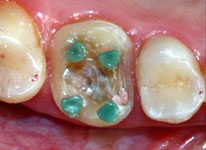

Com a broca tipo trépano (Paramax Drillis 0,7mm OrtoPins da Coltène Whaledent, USA), a qual apresenta limitador de penetração, confeccionou-se quatro perfurações com 2 milímetros de profundidade, localizadas nas regiões correspondentes às bases das cúspides (Fig. 6 e 9). Estes orifícios e a área de atrito friccional conseguida com o bisel chanfrado periférico de forma côncava, evitaram a confecção de núcleo e o preparo para coroa total, preservando a vitalidade pulpar do dente e os limites cervicais localizados supragengivalmente.

Fig. 6

Broca trépano realizando a perfuração na base da cúspide mésio-vestibular.